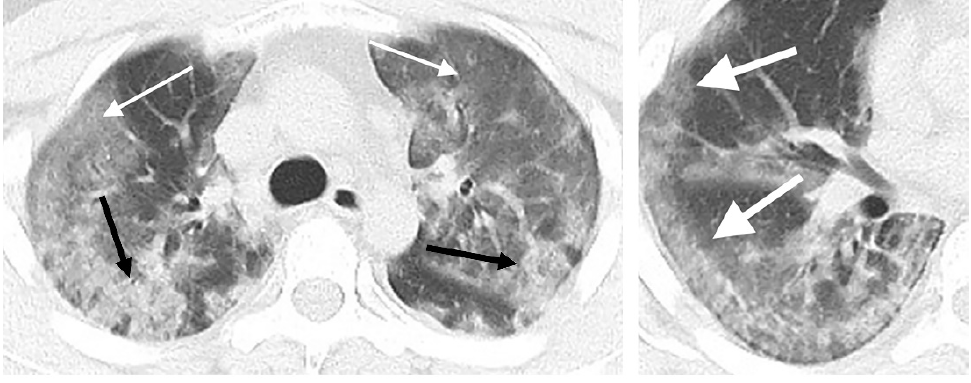

Researchers discuss

#CT features most likely to be seen in coronavirus patients via@AuntMinniehttps://bit.ly/2S18vgpHvala. Twitter će to iskoristiti za poboljšanje vaše vremenske crte. PoništiPoništi -

CT scans of male with novel coronavirus show diffuse bilateral confluent and patchy ground-glass opacities and consolidative opacities (left). A zoomed-in look of the right middle and lower lobes shows striking peripheral distribution (right).

@RSNA http://bit.ly/394duTg pic.twitter.com/GAwtx46jog